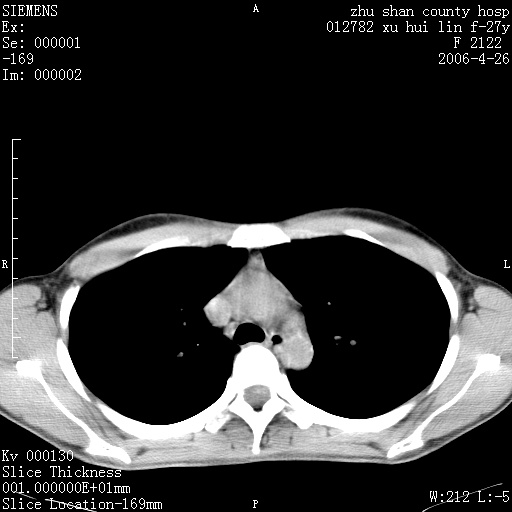

女性 病人 27岁!本院职工家属,五月前因感冒透视发现病变,ct示:左肺下叶背段感染性病变。经过半月规范抗生素治疗后复查病变无明显变化,后行四月规范抗痨治疗,复查无明显变化,后复查无效!请大家帮忙看看!

右肺下叶背段见片状高密度区,边界不清,密度不均,无钙化及空洞影,背段支气管通畅。所见层面肺门及纵隔内未见明显肿大淋巴结影。

女性 病人 27岁!本院职工家属,五月前因感冒透视发现病变,ct示:左肺下叶背段感染性病变。经过半月规范抗生素治疗后复查病变无明显变化,后行四月规范抗痨治疗,复查无明显变化,后复查无效!

诊断:首先还是考虑为慢性炎症。

结核虽然好发于下叶背段,但周围无明显卫星灶,化验结果怎样?